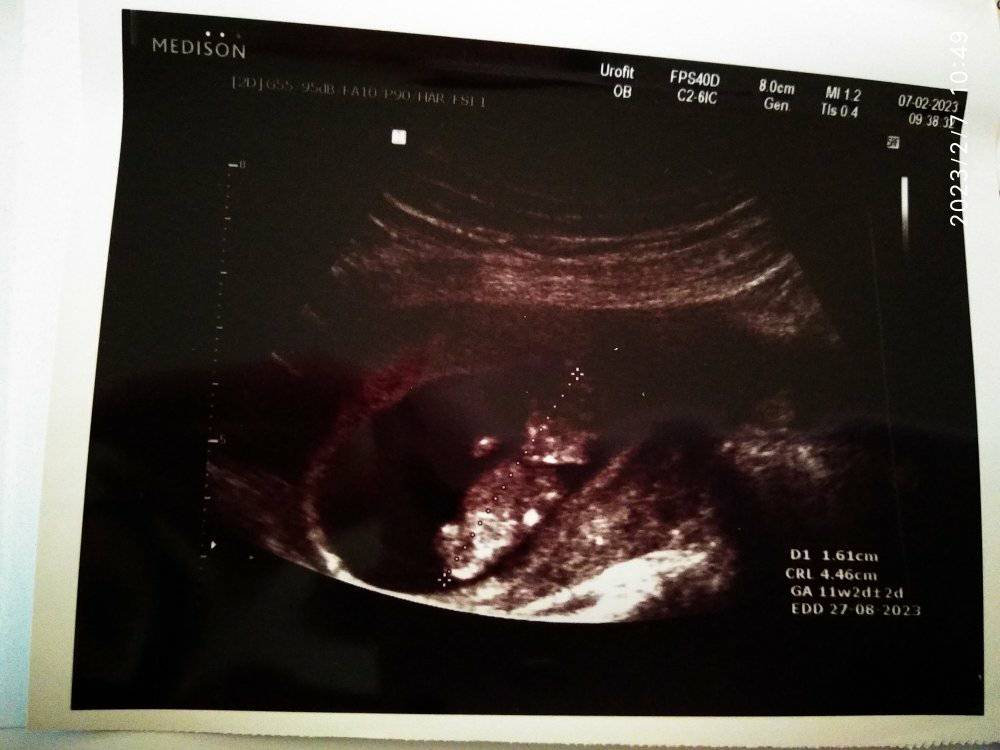

Nub theory guesses

Attachment 43756

I just had my ultrasound at 10w6d, and I am hoping some of you would like to guess if it's a girl or a boy. I am not sure if it's too soon for the nub theory but it's worth taking a shot until I get my NIPT test results, then I will know for sure. :baby2: